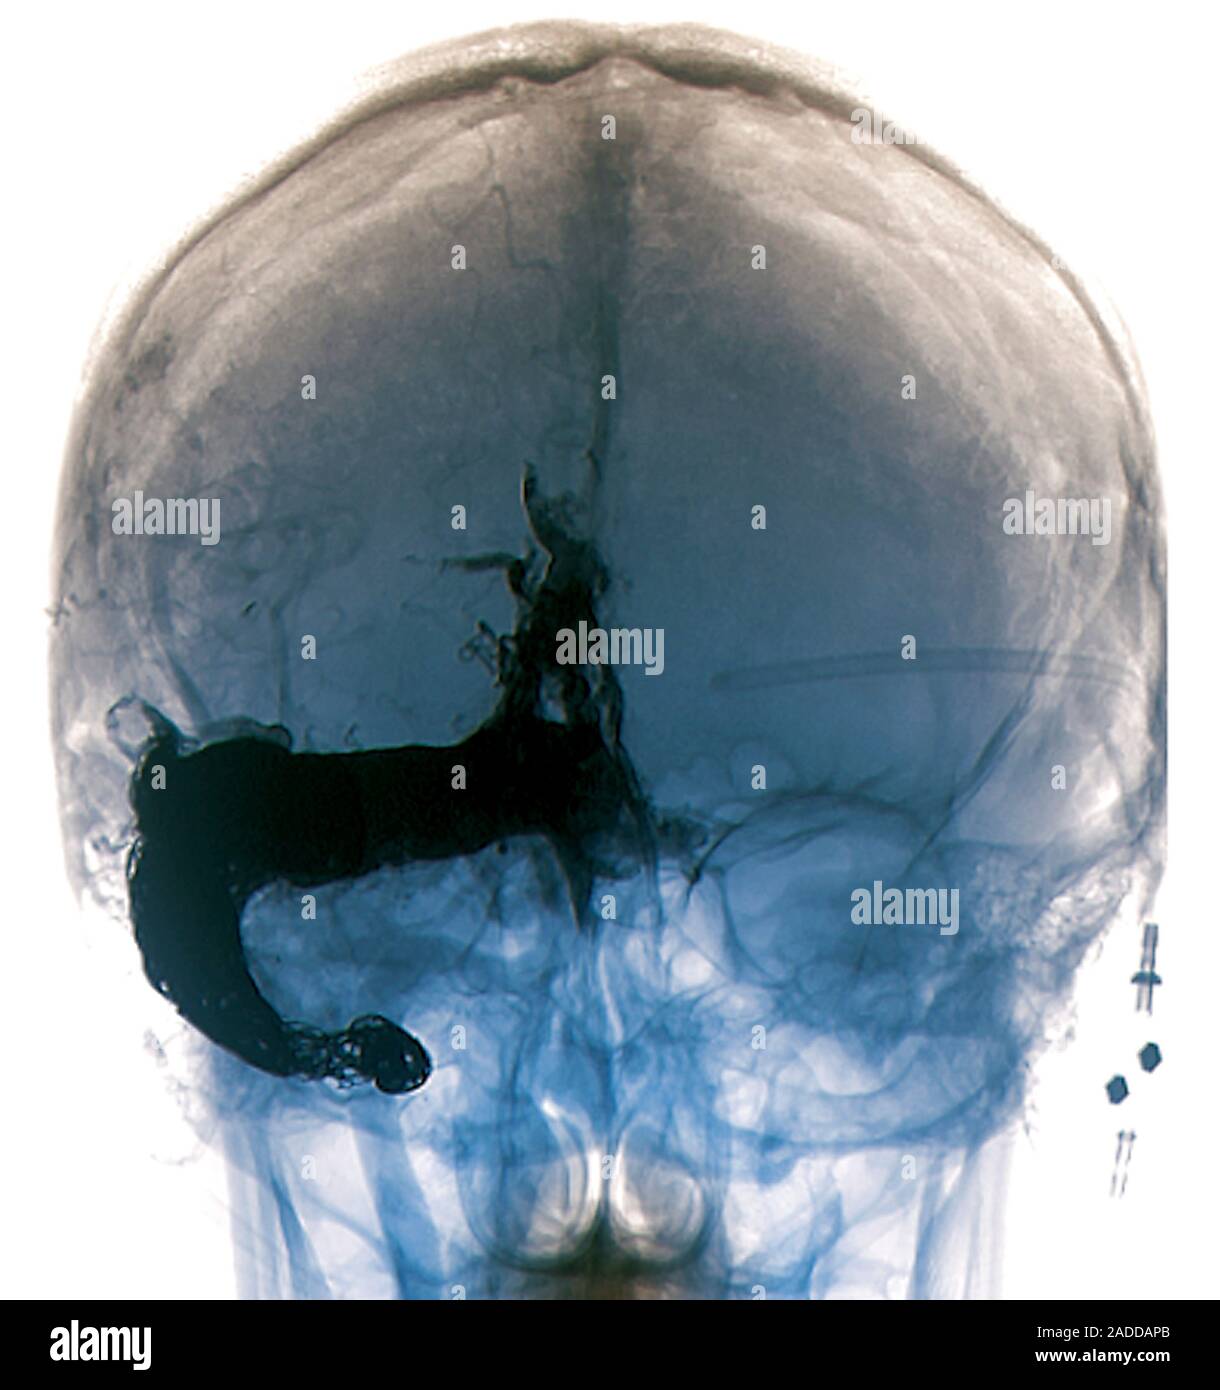

From www.alamy.com

Cerebral arteriovenous malformation. Threequarter posterior Xray of the skull and brain of a An Arteriovenous Malformation An arteriovenous malformation (avm) is a tangle of blood vessels that can pose a risk of rupture and bleeding. Arteriovenous malformations (avms) happen when a group of blood vessels in your body forms incorrectly. The tangle is made of. If they rupture, they may be life. Learn how doctors treat it. To diagnose an avm, your health care provider will. An Arteriovenous Malformation.